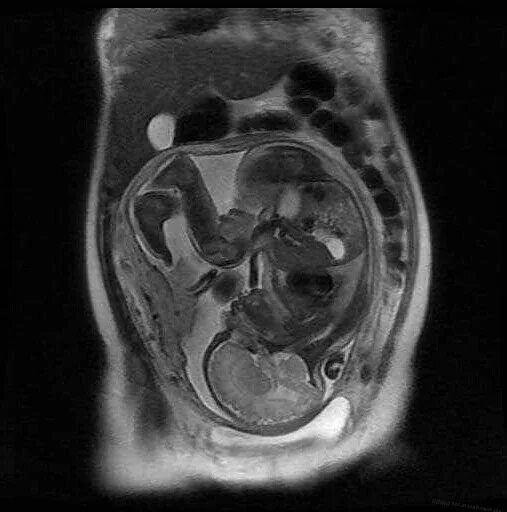

Мрт беременной